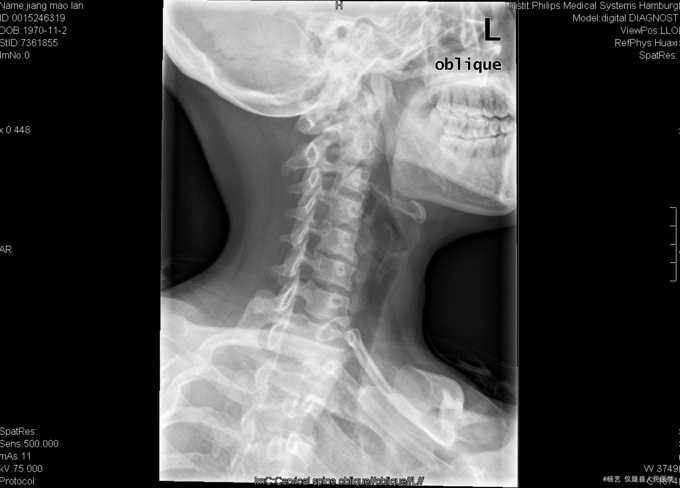

患者蒋茂兰,女,45岁0月,因“头晕伴视物旋转10+月,加重1+月。”入院 10+月前患者无明显诱因出现头晕、头昏;视物旋转,偶伴有呕吐,呕吐为胃内容物;间断发作,发作时持续时间不等,休息后明显缓解。无活动障碍;无肢体麻木、乏力;无行走不稳;无发热、头痛等,1+月前患者上述症状加重,患者于当地医院就诊,治疗未见明显好转。颈椎MRI示:颈5/6椎间盘突出。现患者为求进一步诊治就诊于我院,门诊以“C5/6椎间盘突出症伴脊髓神经不全损害”收入我科。

查体:T:36.9oC,P:78次/分,R:19次/分,BP:109/72mmHg。神志清楚,无病容,皮肤巩膜无黄染,全身浅表淋巴结未见肿大。。颈静脉正常。心界正常,心律齐,各瓣膜区未闻及杂音。胸廓未见异常,双肺叩诊呈清音,双肺呼吸音清,未闻及干湿啰音及胸膜摩擦音。腹部外形正常,全腹柔软,无压痛及反跳痛,腹部未触及包块,肝脏肋下未触及,脾脏肋下未触及,双肾未触及。双下肢无水肿。 专科查体:视:脊柱外观无畸形,活动无异常,无皮肤破溃及窦道形成。触:椎体棘上、椎旁肌无压痛、叩痛,四肢感觉无明显减退,远端血运未见异常。动量:颈部屈伸、左右侧偏活动无明显受限,双上肢耸肩、屈伸肘关节、屈伸腕肌力5级,双手握力5级,双下肢伸髋、屈髋、外展、内收、伸膝、屈膝肌力5级,双足趾背伸肌力5级。双侧肱二、三头肌肌腱反射、膝腱反射、跟腱反射正常引出。双侧Hoffmann氏征阳性,Babinski征阴性,踝阵挛阴性,髌阵挛阴性。 辅助检查:外院MRI示:颈椎退行性变,颈5/6椎间盘突出。垂体区:空泡蝶鞍?

综上初步诊断:1、颈5-6椎间盘突出症伴脊髓神经不全损害;2、白癜风 经前路颈5/6椎间盘切除、椎管及椎间孔减压、椎间融合器植骨融合内固定术。 手术发现:  颈5/6椎间隙变窄,椎间盘髓核干涩,无光泽。颈5/6椎间隙后份少量骨赘生成,椎间盘向后方突出,压迫硬脊膜。术中夹出数块突入椎管内的椎间盘髓核组织及增生骨赘。充分减压后,可见硬脊膜恢复膨隆,双侧神经根松弛,术中未见脑脊液漏。